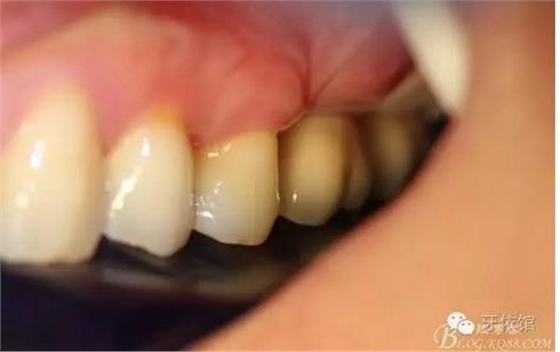

戴入后口內(nèi)照